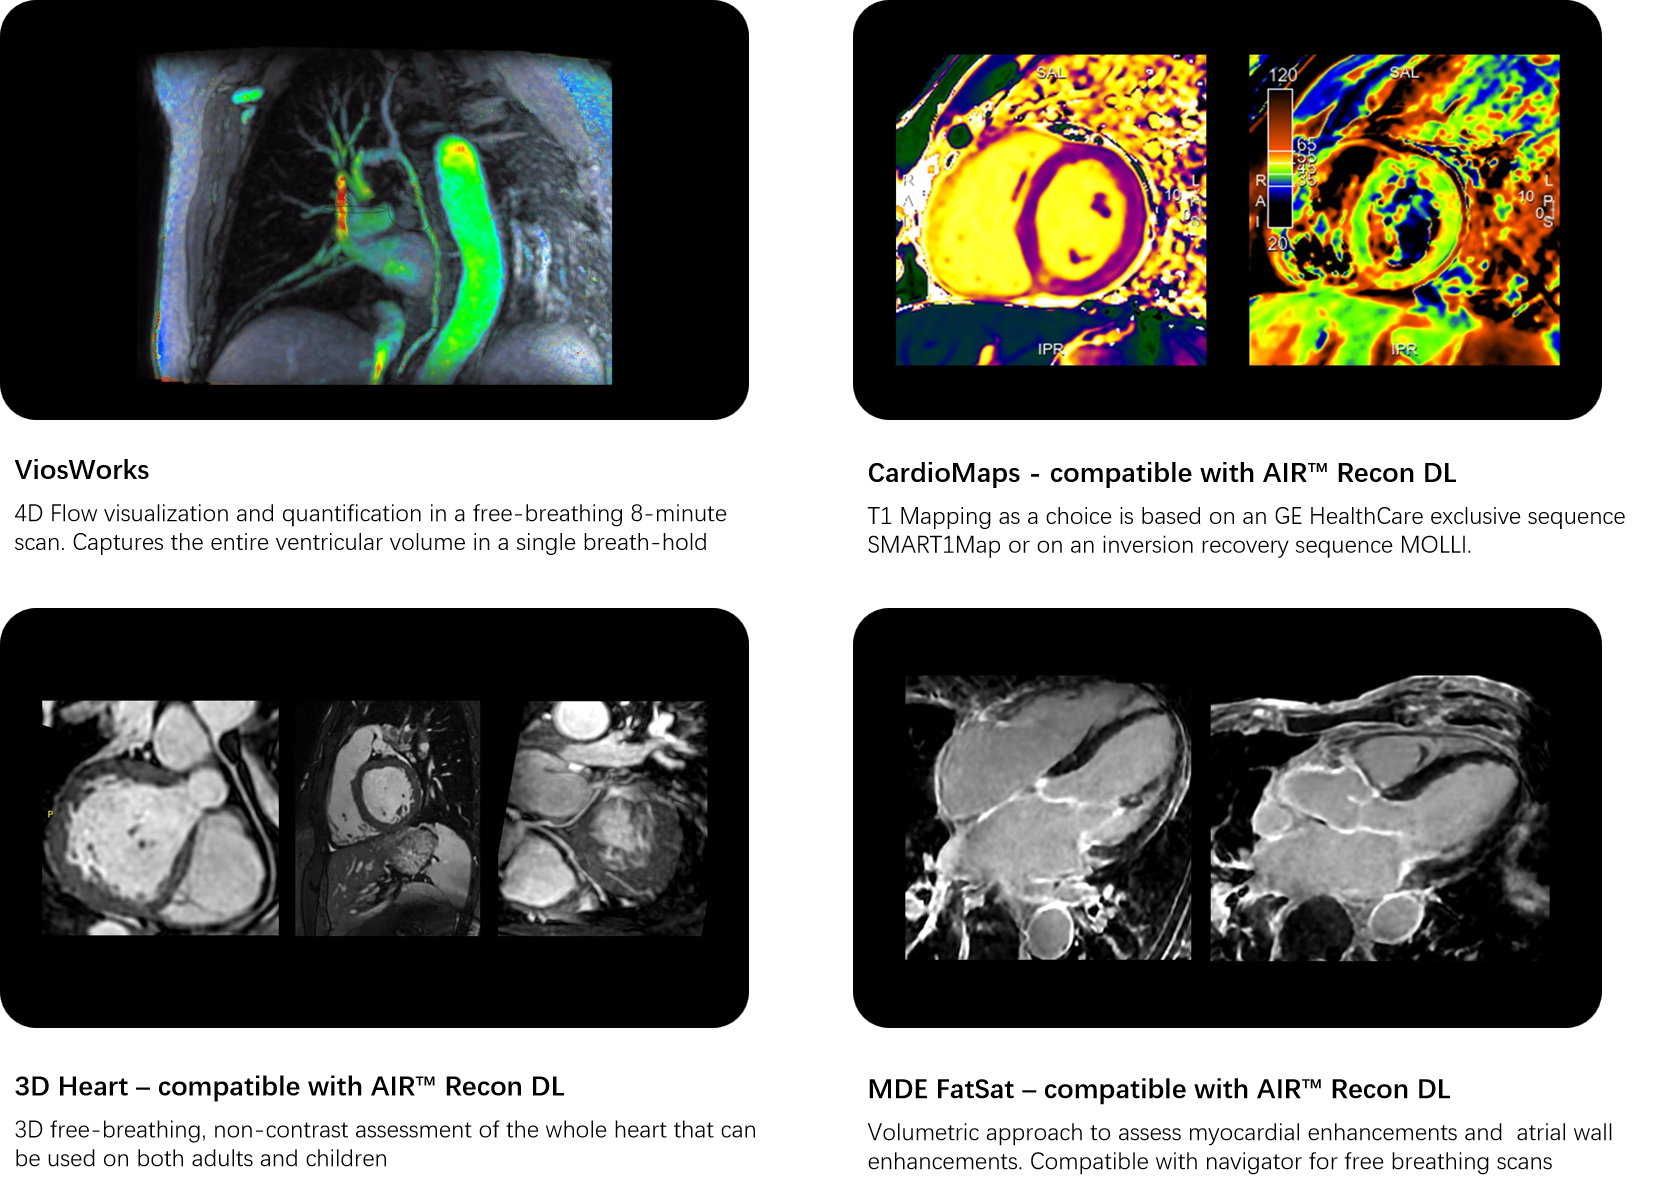

Wide range of MR cardiovascular imaging techniques to assess morphology, flow, function and tissue viability while adapting to a wide variety of patient types.

Cardiovascular MRI imaging applications

A COMPLETE CARDIAC PACKAGE

unBEATable SIGNA™ Cardiac MR Cardiac MR has been too slow, complex and inconsistent for too long1. Now with cardiac MR for SIGNA™, that’s all in the past. Experience accelerated diagnostics and crystal-clear imaging, powered by deep learning. From AI-boosted precision to lightning-fast scans, explore the seamless connection between innovation and patient-centric care..